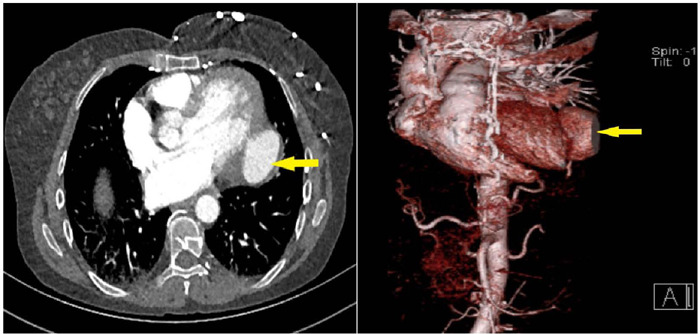

Systemic lupus erythematosus is a clinically heterogeneous autoimmune disease that frequently affects young women. The risk of cardiovascular events is higher in patients with this disease than in the general population. In this study, we report a patient who developed a left ventricular pseudoaneurysm with no etiological factor other than systemic lupus erythematosus. Dor ventriculoplasty and mitral ring replacement were performed as surgical treatment. The case is shared because of the rarity of left ventricular pseudoaneurysm due to systemic lupus erythematosus and successful pseudoaneurysm repair.